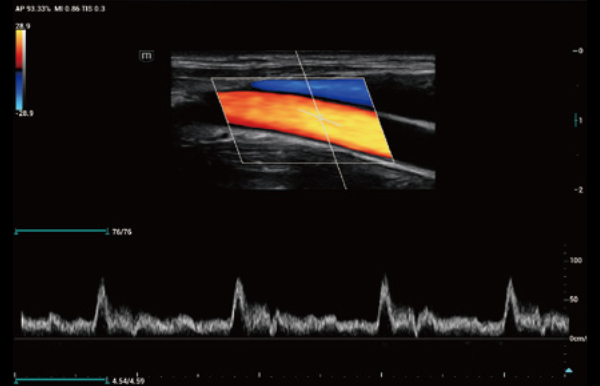

Uitgebreide?oplossingen voor beeldvorming aangestuurd door ZST?+

Het ZST+?platform is een buitengewone innovatie en revolutie in de wereld van echografie. Het transformeert echografiegegevens van conventionele bundelvorming naar kanaalgegevensverwerking. Het overwint de traditionele afweging tussen ruimtelijke resolutie, temporele resolutie en weefseluniformiteit, en levert een uitzonderlijke beeldkwaliteit voor oneindige beeldvormingsoplossingen met non-stop verbeteringen.